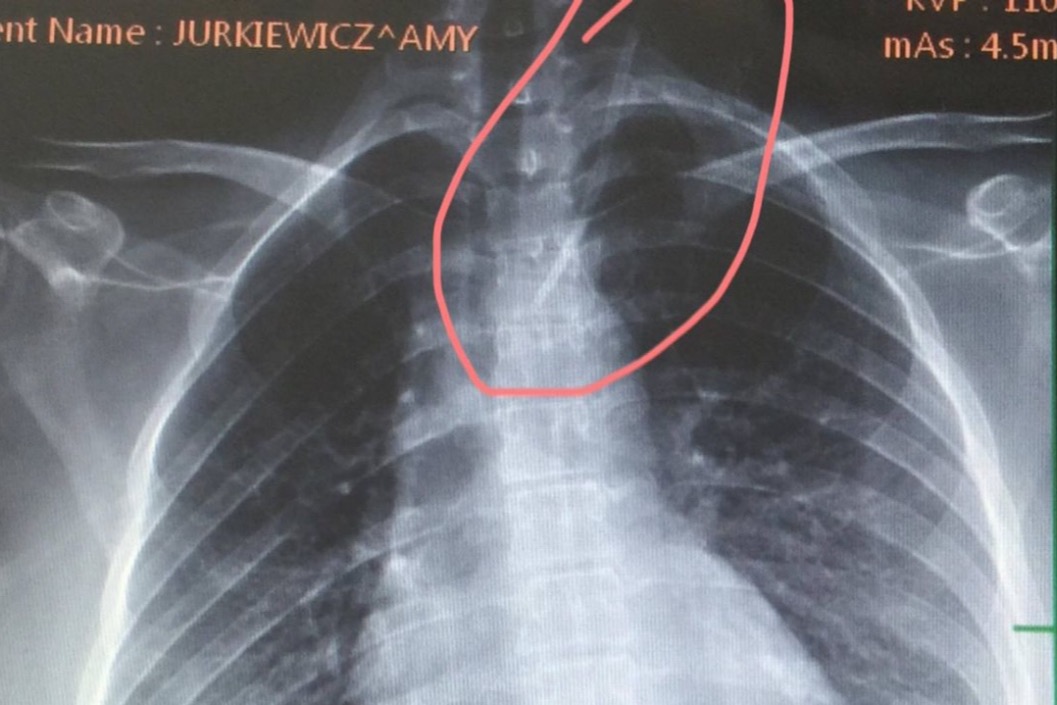

As some of you may know, I was paralyzed in July of 2016. Several weeks of doctors ignoring my plea for help & giving me norcos, turned into me spending several weeks sleeping on my back in Neurology ICU at University of Chicago receiving plasmapheresis.